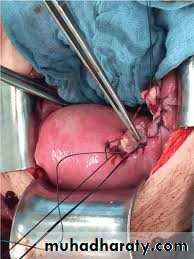

3-immediate laparotomy

4-deliver the fetous & placenta

5-explore the rupture site.

...if it's amenable for repair & the patient didn't complete her family....repair is done.

...if it's not amenable for repair...hysterectomy is done.

6-exploration of the other viscera mainly the bladder .